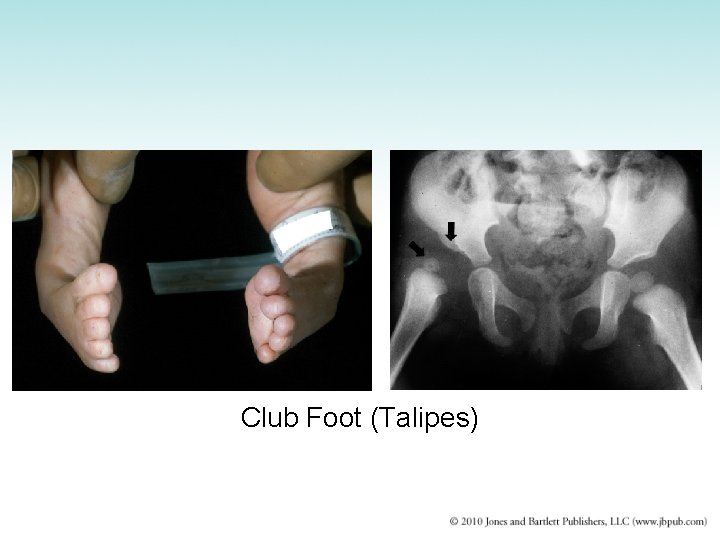

Congenital Malformations (2 of 2) • Congenital clubfoot (talipes) – Multifactorial inheritance – Most common type: talipes equinavarus – Treatment: manipulation and casts • Congenital dislocation of the hip – Multifactorial inheritance – More common in females – Shallow acetabulum causes femoral head to be displaced out of socket – Breech position favors development – Treatment: manipulation and casts

Club Foot (Talipes)